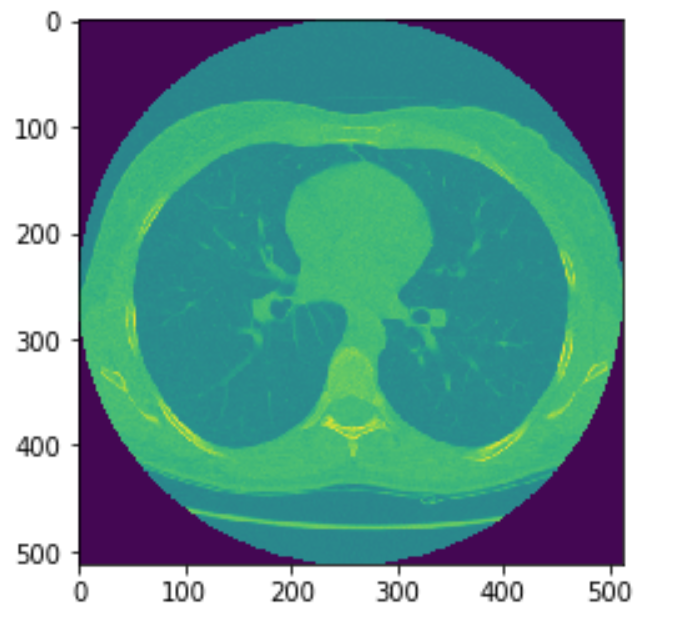

plt.imshow(img_grow_arr_Confidence[68])

结果上有很多的空洞需要填补。